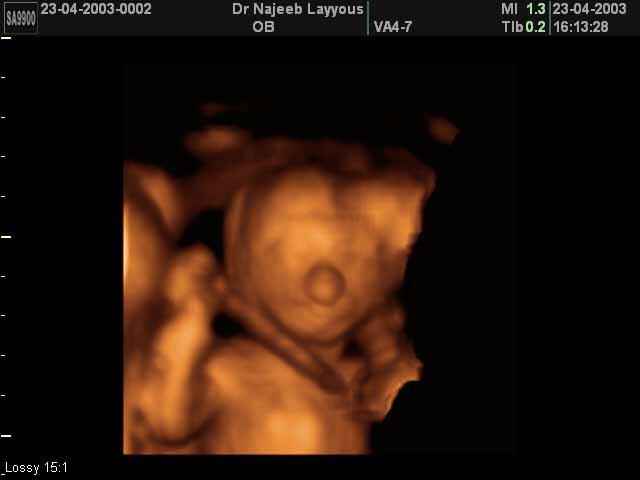

- Fetal Face Ultrasound Photos

- 3D Fetal Profile Ultrasound Scan Photos

- Fetal Behavior Ultrasound Photos

- The Clinical Advantages of 3D and 4D Ultrasound

- Definition and Features of Four Dimensional Ultrasound

- Uses of 4D Ultrasound scan

- The importance of 4D ultrasound imaging in pregnancy

3D Second Trimester Ultrasound Scan Photos-second part of pregnancy | Dr N Layyous